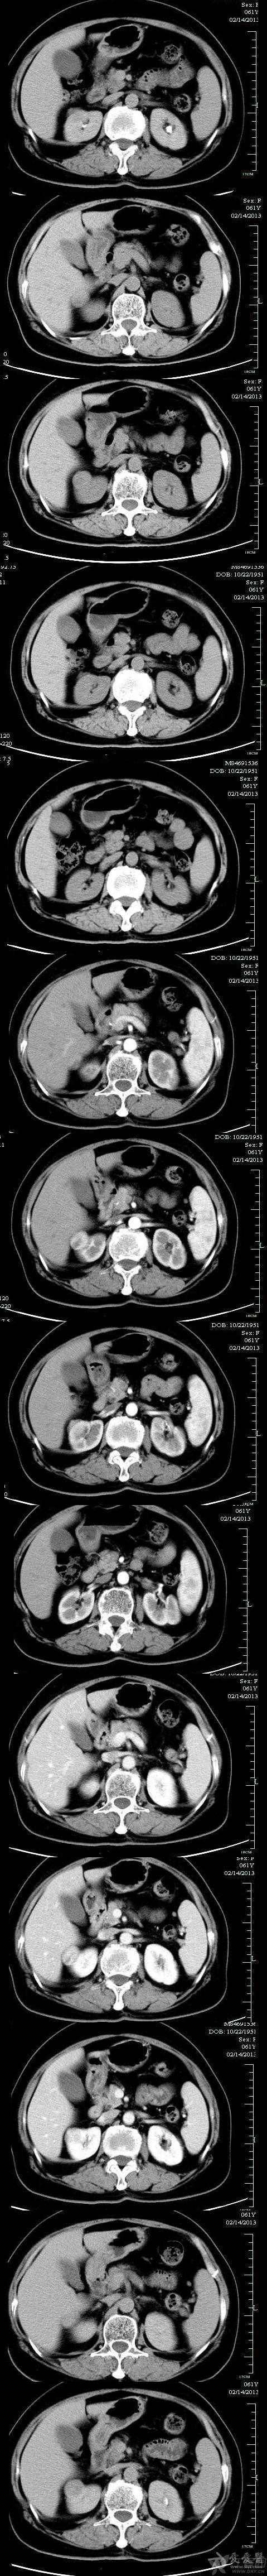

【clear柯丽尔每日一例】右肾透明细胞癌(clear cell carcinoma)ct

图片尺寸600x690